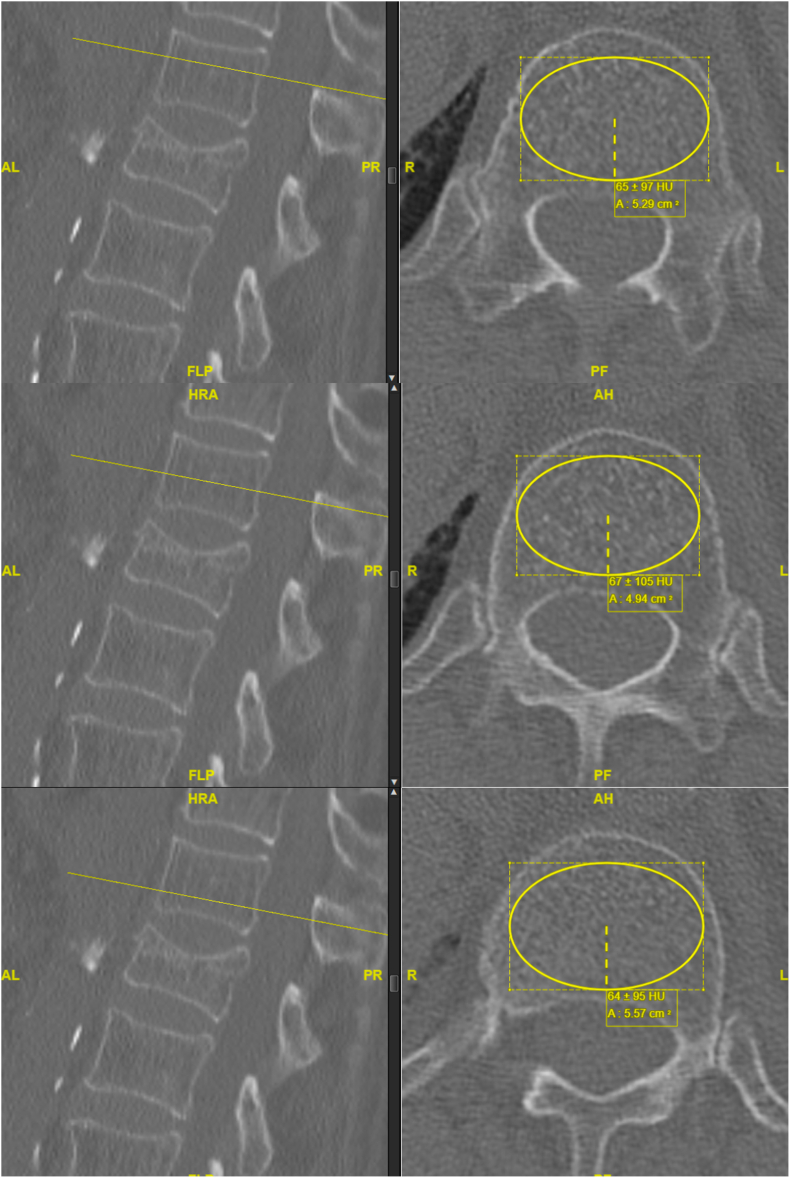

Objective: This study aims to assess the utility of Hounsfield units (HU) derived from computed tomography (CT) scans as a predictive marker for the risk of adjacent fractures (AF) following kyphoplasty.

Methods: In a retrospective analysis at a high-volume care hospital, 93 patients who underwent single-level kyphoplasty between January 2012 and December 2020 were included. The study focused on the correlation between HU values in vertebrae adjacent to the operated level and the occurrence of AF. Patient demographics, fracture characteristics, and time to AF occurrence were recorded. Bone density was assessed using HU measurements from CT scans, focusing on the trabecular bone.

Results: The median time to AF occurrence was 10 weeks, with no significant correlation to patient demographics or fracture location. A marked association was observed between reduced bone density, as measured by HU in the vertebrae adjacent to the kyphoplasty site, and the incidence of AF. Particularly, the bone density in the vertebra immediately superior to the operated site showed a statistically significant relationship with the occurrence of AF.